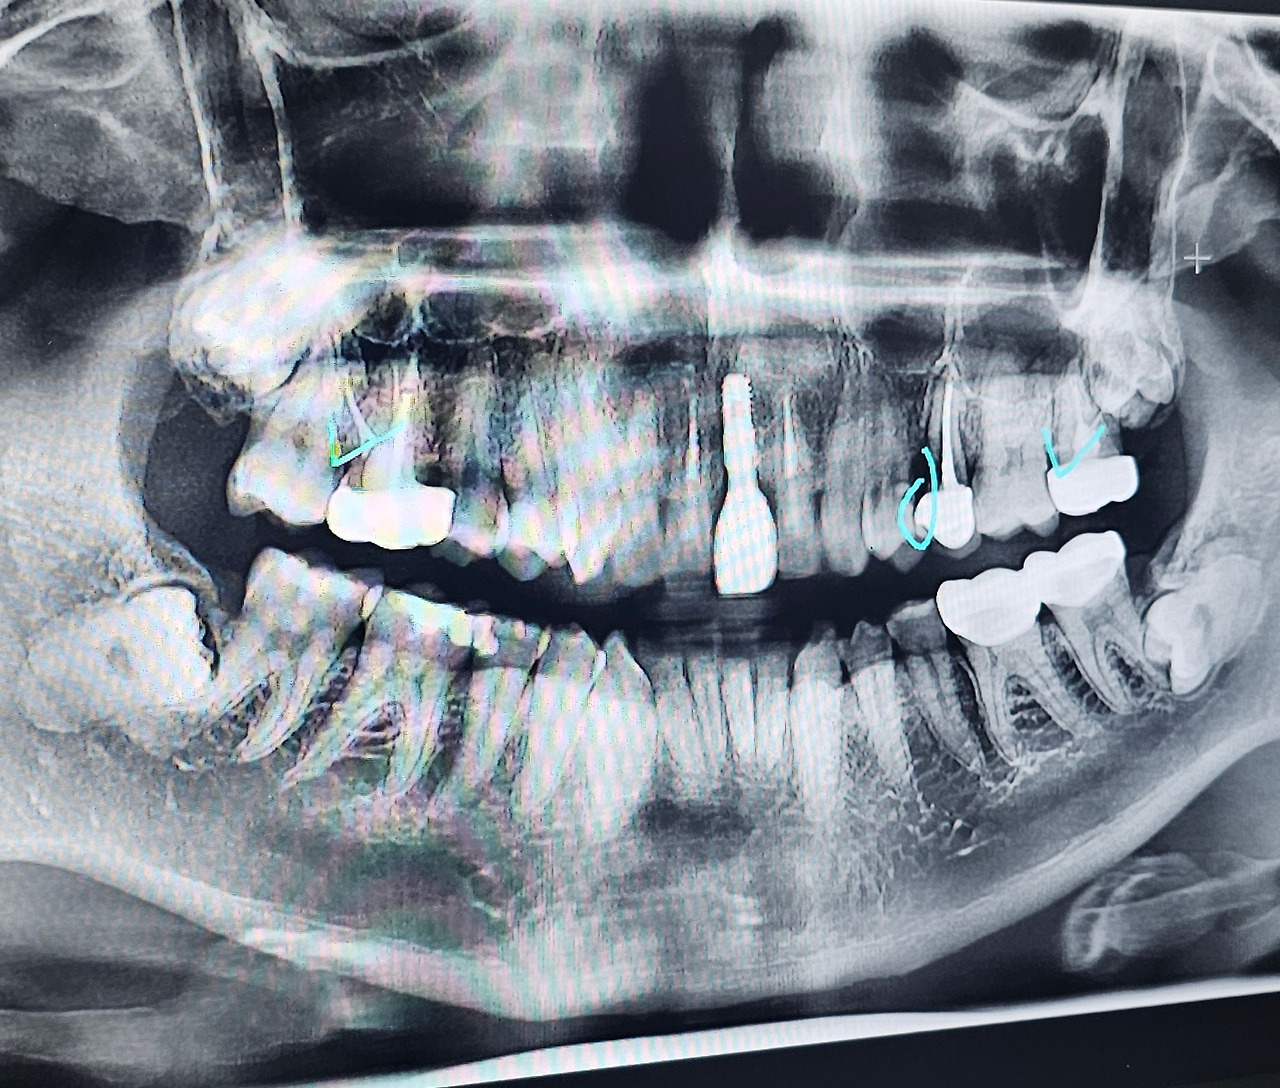

이거 이러다 큰일이 날 거 같아 급하게 갈 수 있는 가까운 치과로 갔다. 처음 가는 곳이어서 입안 전체적인 사진을 찍고 선생님과 함께 내 잇몸을 보았다. 선생님께서는 내 사진을 쓰윽 둘러보시고 직접 입안을 확인하시는데 부은 내 잇몸을 보자마자 나지막이 말하셨다.

많이 부었던 내 잇몸은 언제 부었냐는 듯이 완전히 가라앉았고 치과에서도 다행이라고 하셨다. 하지만 발치라는 얘기가 나왔으니 안심할 수 없는 부분. 이제부터는 어떤 치료를 받을지 걱정을 했다. 선생님께서는 내 엑스레이 사진을 보여주시면서 현재 이빨 상황에 대해 다시 설명해 주셨다.

잇몸이 부었던 이빨이 치료가 잘못되어서 거기로 이물질이 들어가 잇몸이 부은 거 같다고 하셨다. 그래서 거기를 인레이치료를 해서 막아주고 썩은 부분을 긁어낼 거라고 하셨다. 다행히 임플란트얘기는 안 나왔다. 치료받아야 할 이빨을 설명해 주시면서 전반적인 부분도 설명해 주셨는데 반대쪽 치아도 똑같이 진행이 되어서 여기도 같이 치료를 해야 한다고 하셨다.

임플란트를 하지 않아 안도했는데 충치가 있다는 얘기에 좀 놀랐다. 분명 기존 병원에서는 충치가 없다고 했었는데. 그렇지 충치가 없었다면 잇몸이 붓지도 않았을 것이다. 결국 나는 치료를 받기로 하며 그날 비용이 좀 많이 나가게 되었다.

사랑니를 보아 전생에 죄를 지은게 분명하다